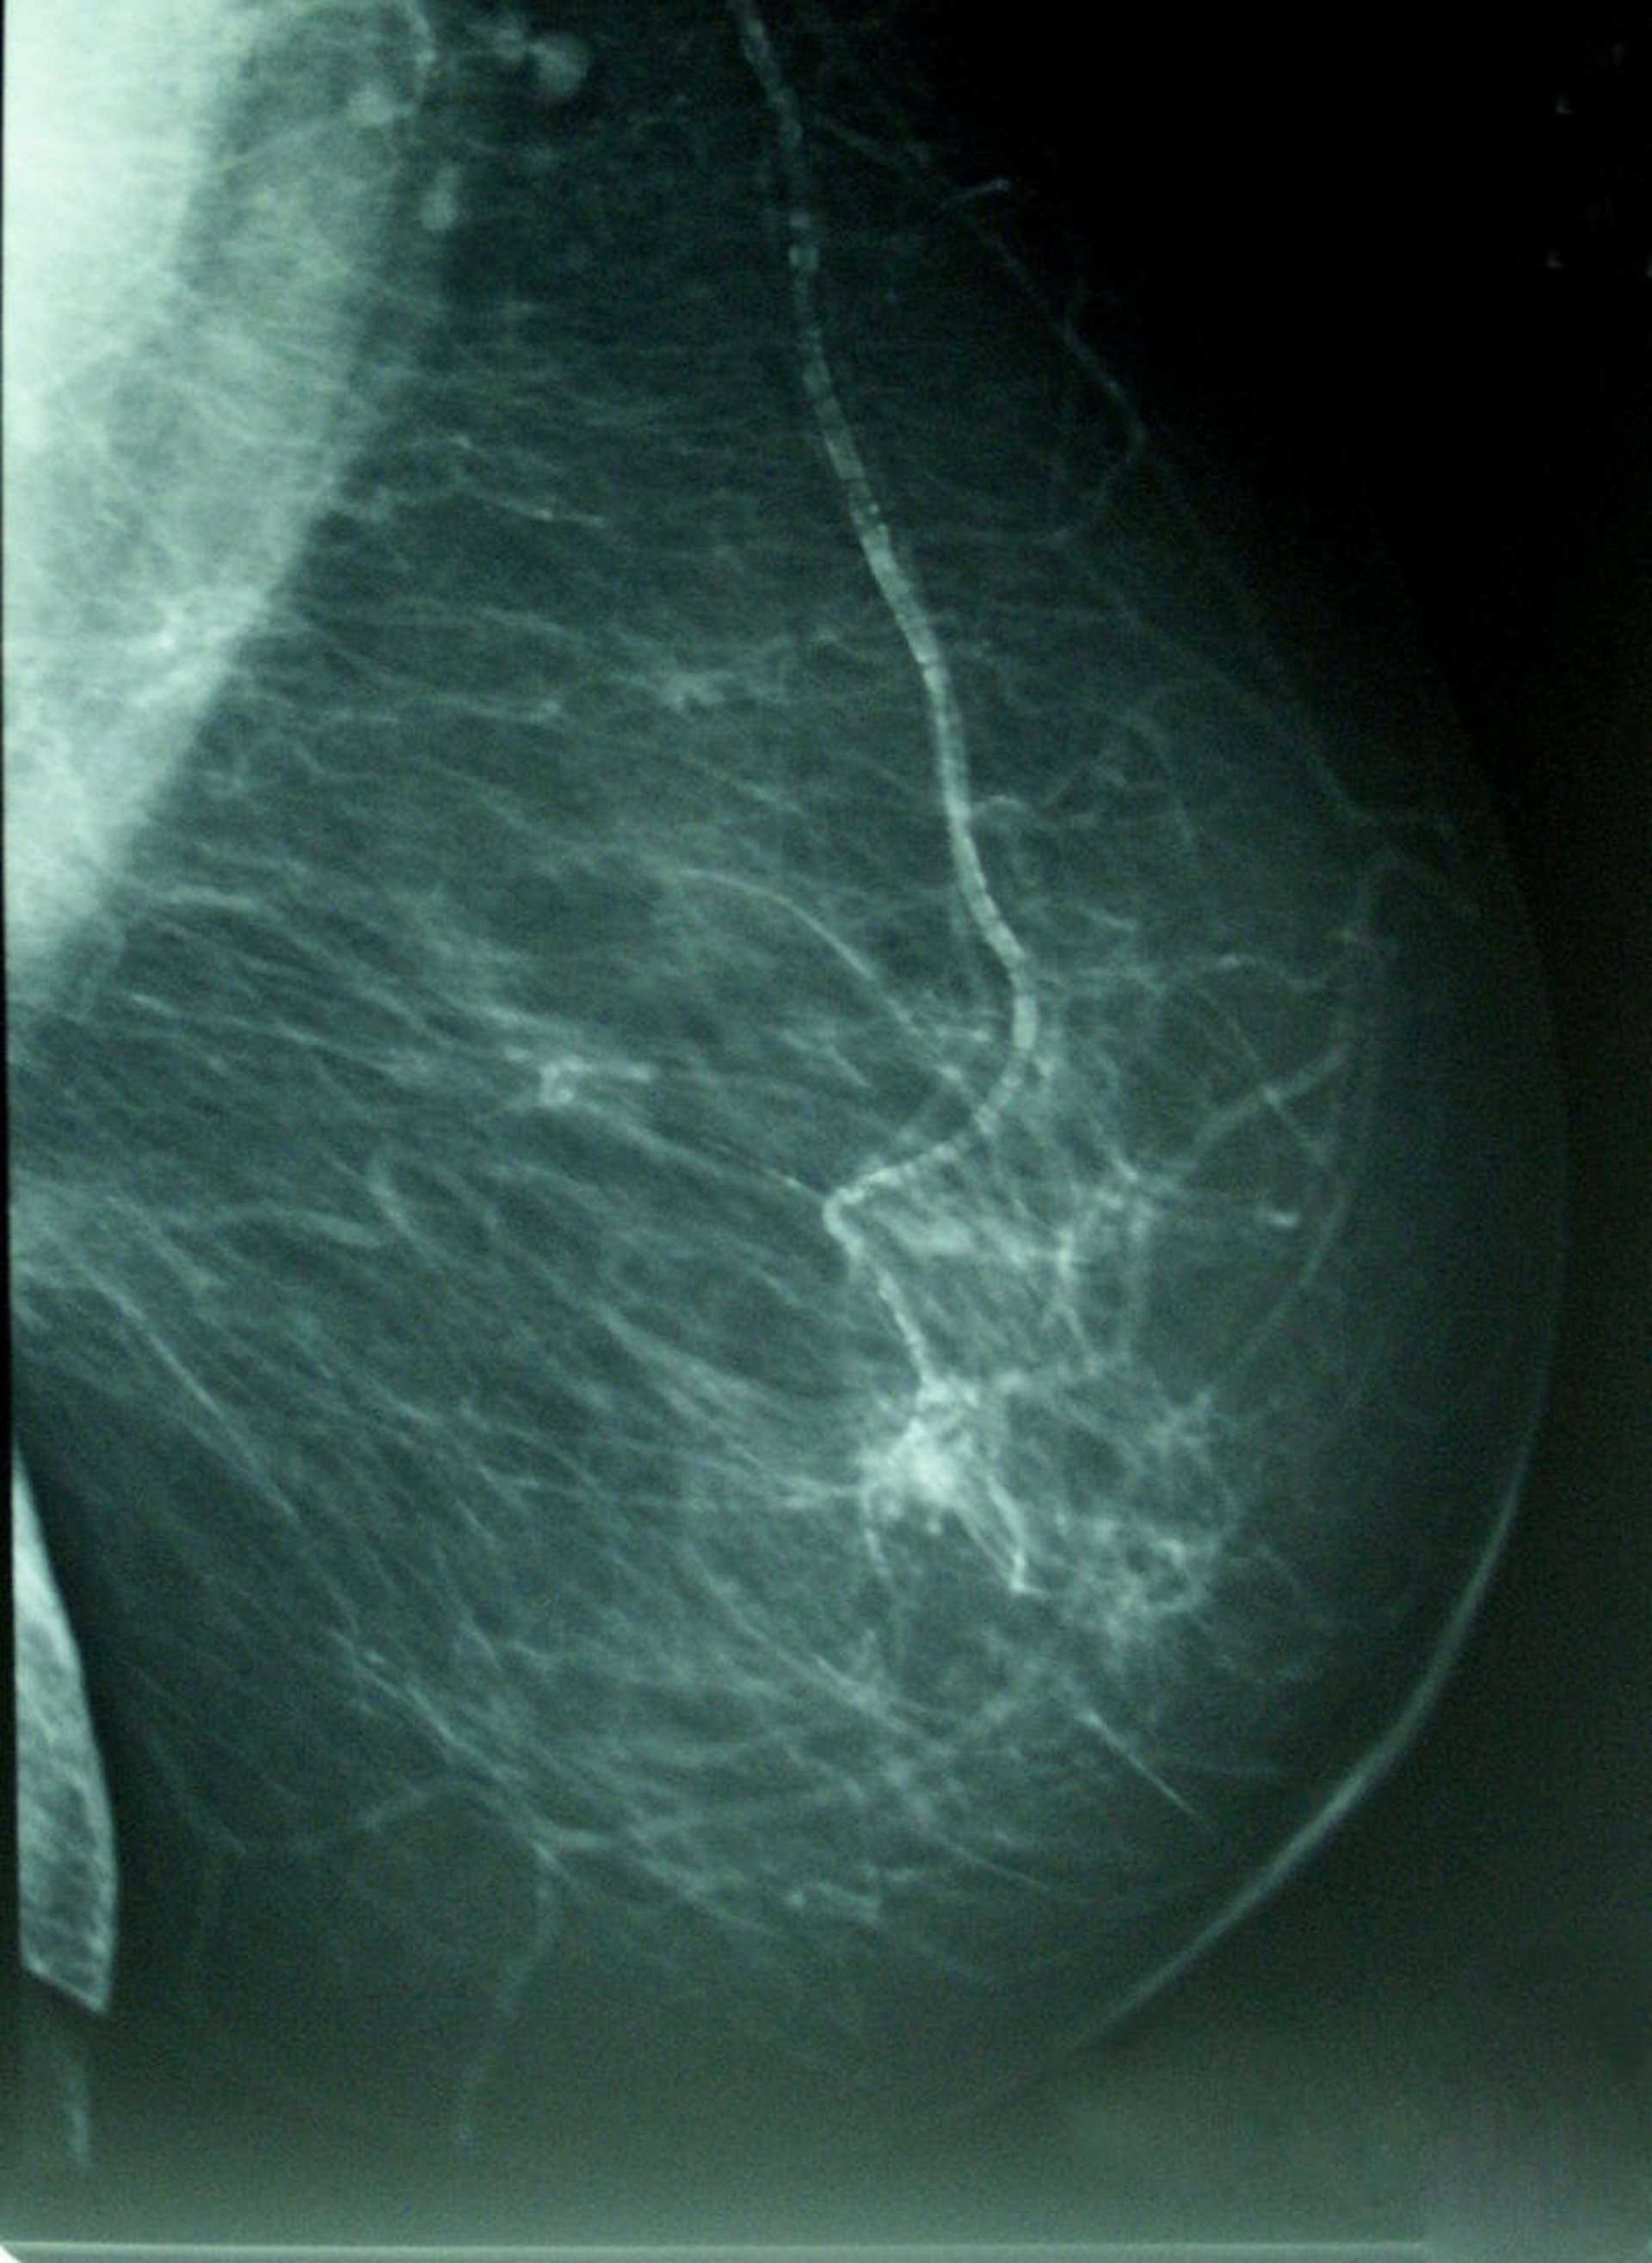

Cáncer De Mama, Densidad Mamográfica

Entre 2 y 4 mujeres de cada 10 van a padecer un cáncer a lo largo de su vida, y de ellos, el más frecuente es el cáncer de mama, del que se diagnostican 22.000 nuevos casos al año en España. Ante esta probabilidad, los médicos recomiendan "aceptar el riesgo" y participar en los programas de cribado -mamografía y ecografía de mama-, incluyendo también el importantísimo autochequeo.